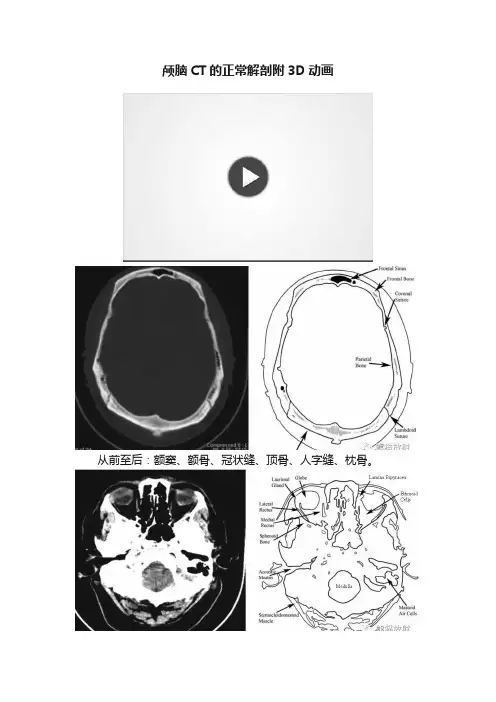

颅脑CT的正常解剖附3D动画

从前至后:额窦、额骨、冠状缝、顶骨、人字缝、枕骨。

右侧从前至后:眼球、泪腺、外直肌、内直肌、蝶骨、耳道、胸锁乳突肌;

左侧从前至后:纸板、筛窦气房(箭头位置应内移至近中线处)、乳突气房、脊髓。